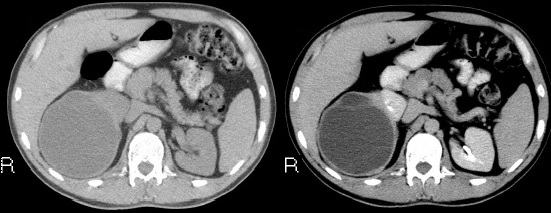

Fase corticomedular y arterial

Esta primera fase ocurre en los primeros 25 a 70 segundos posteriores a la inyección del medio de contraste; la corteza renal, al retener el medio de contraste en este tiempo en los capilares corticales aumenta de una manera intensa diferenciándose de la médula renal, que se encuentra hipodensa.

La fase arterial o corticomedular es esencial para la estadificación, extensión y planificación quirúrgica, si fuese el caso de la neoplasia encontrada, ya que ofrece un mejor detalle vascular (opacificación de los vasos), una mayor definición anatómica y de lesiones vascularizadas en el hígado, el bazo o el páncreas, consideradas dentro del contexto de una metástasis (Fig. 2).

Los errores diagnósticos que pueden presentarse durante esta fase se asocian a lesiones de pequeño tamaño; en el caso de un tumor hipervascularizado pequeño aumentaría su atenuación en la misma medida en que lo haría la corteza. Otro error que puede ocurrir es con los tumores pequeños que se localizan hacia la médula, ya que por su ubicación se mantendrían hipodensos durante esta fase 3-4.